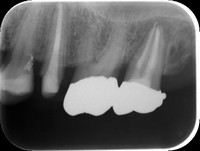

当院における歯周組織再生療法の一例

原因を取り除き、適正な処置を行うことで、白矢印部の骨が回復しているのがわかると思います。